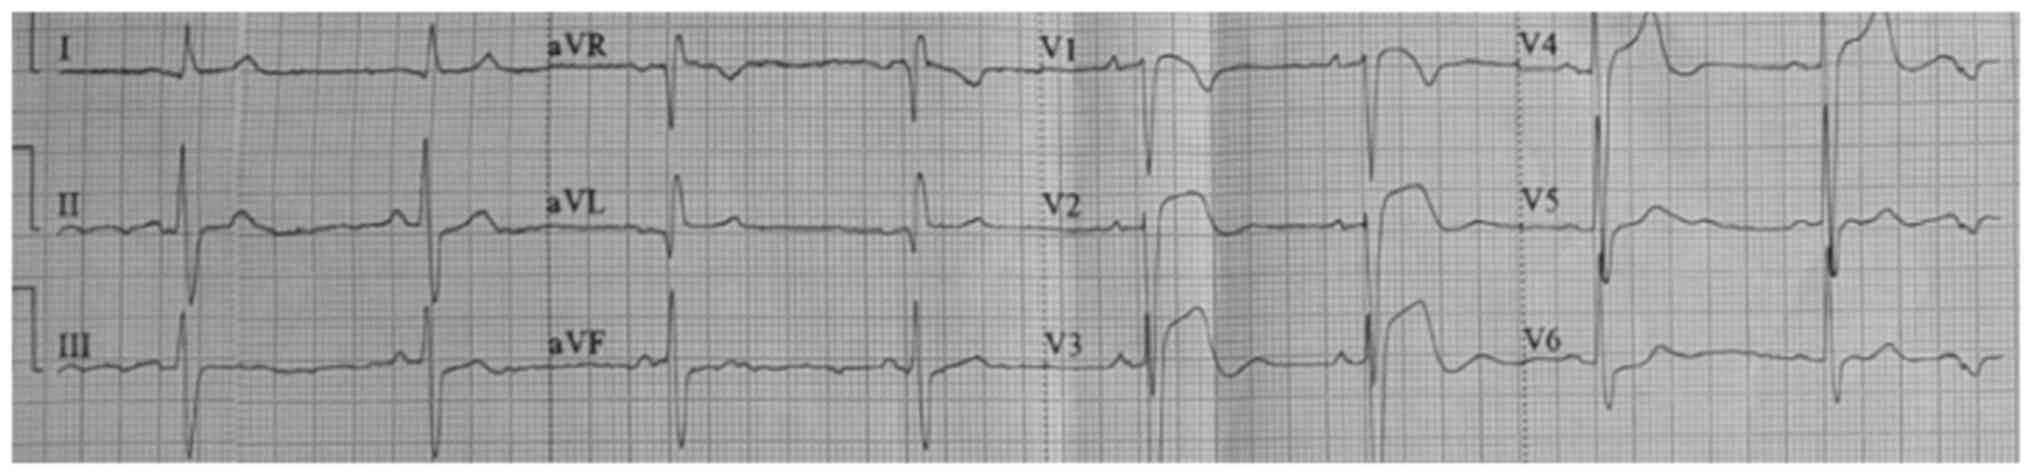

A 78-year-old male patient was transferred from a lower-complexity to a high-complexity hospital in August 2021 because imaging and hemodynamic services were unavailable in the former setting. At the lower-complexity hospital, the patient presented with weakness and decreased muscle strength in the left half of the body with 2 h of evolution, which was associated with dysarthria and deviation of the right labial commissure. The patient was admitted with elevated blood pressure (220/110 mmHg), for which 20 mg of labetalol was administered intravenously. An ECG was immediately performed, which revealed elevation of the ST segment, a situation that was managed pharmacologically as a myocardial infarction by administering 80 mg of atorvastatin and 300 mg of clopidogrel. Subsequently, the patient was transferred to a higher-complexity hospital, where it was observed that the patient neither had a history of angina or dyspnea, nor symptoms of a coronary syndrome. Fig. 1 presents ST-segment elevation in V1, V2 and V3 (acquired at the low-complexity hospital). Fig. 2 depicts ST-segment elevation in V3 and V4 (acquired at the high-complexity hospital) and Fig. 3 presents right temporal intraparenchymal hematoma with vasogenic edema and ventricular involvement (acquired at the high-complexity hospital).

Figure 1

Electrocardiogram performed at the low-complexity hospital in August 2021 during the first 10 min after the patient's admission to the hospital. Sinus rhythm and a heart rate of 49 beats per min were observed, and ST-segment elevation was detected in V1, V2 and V3.